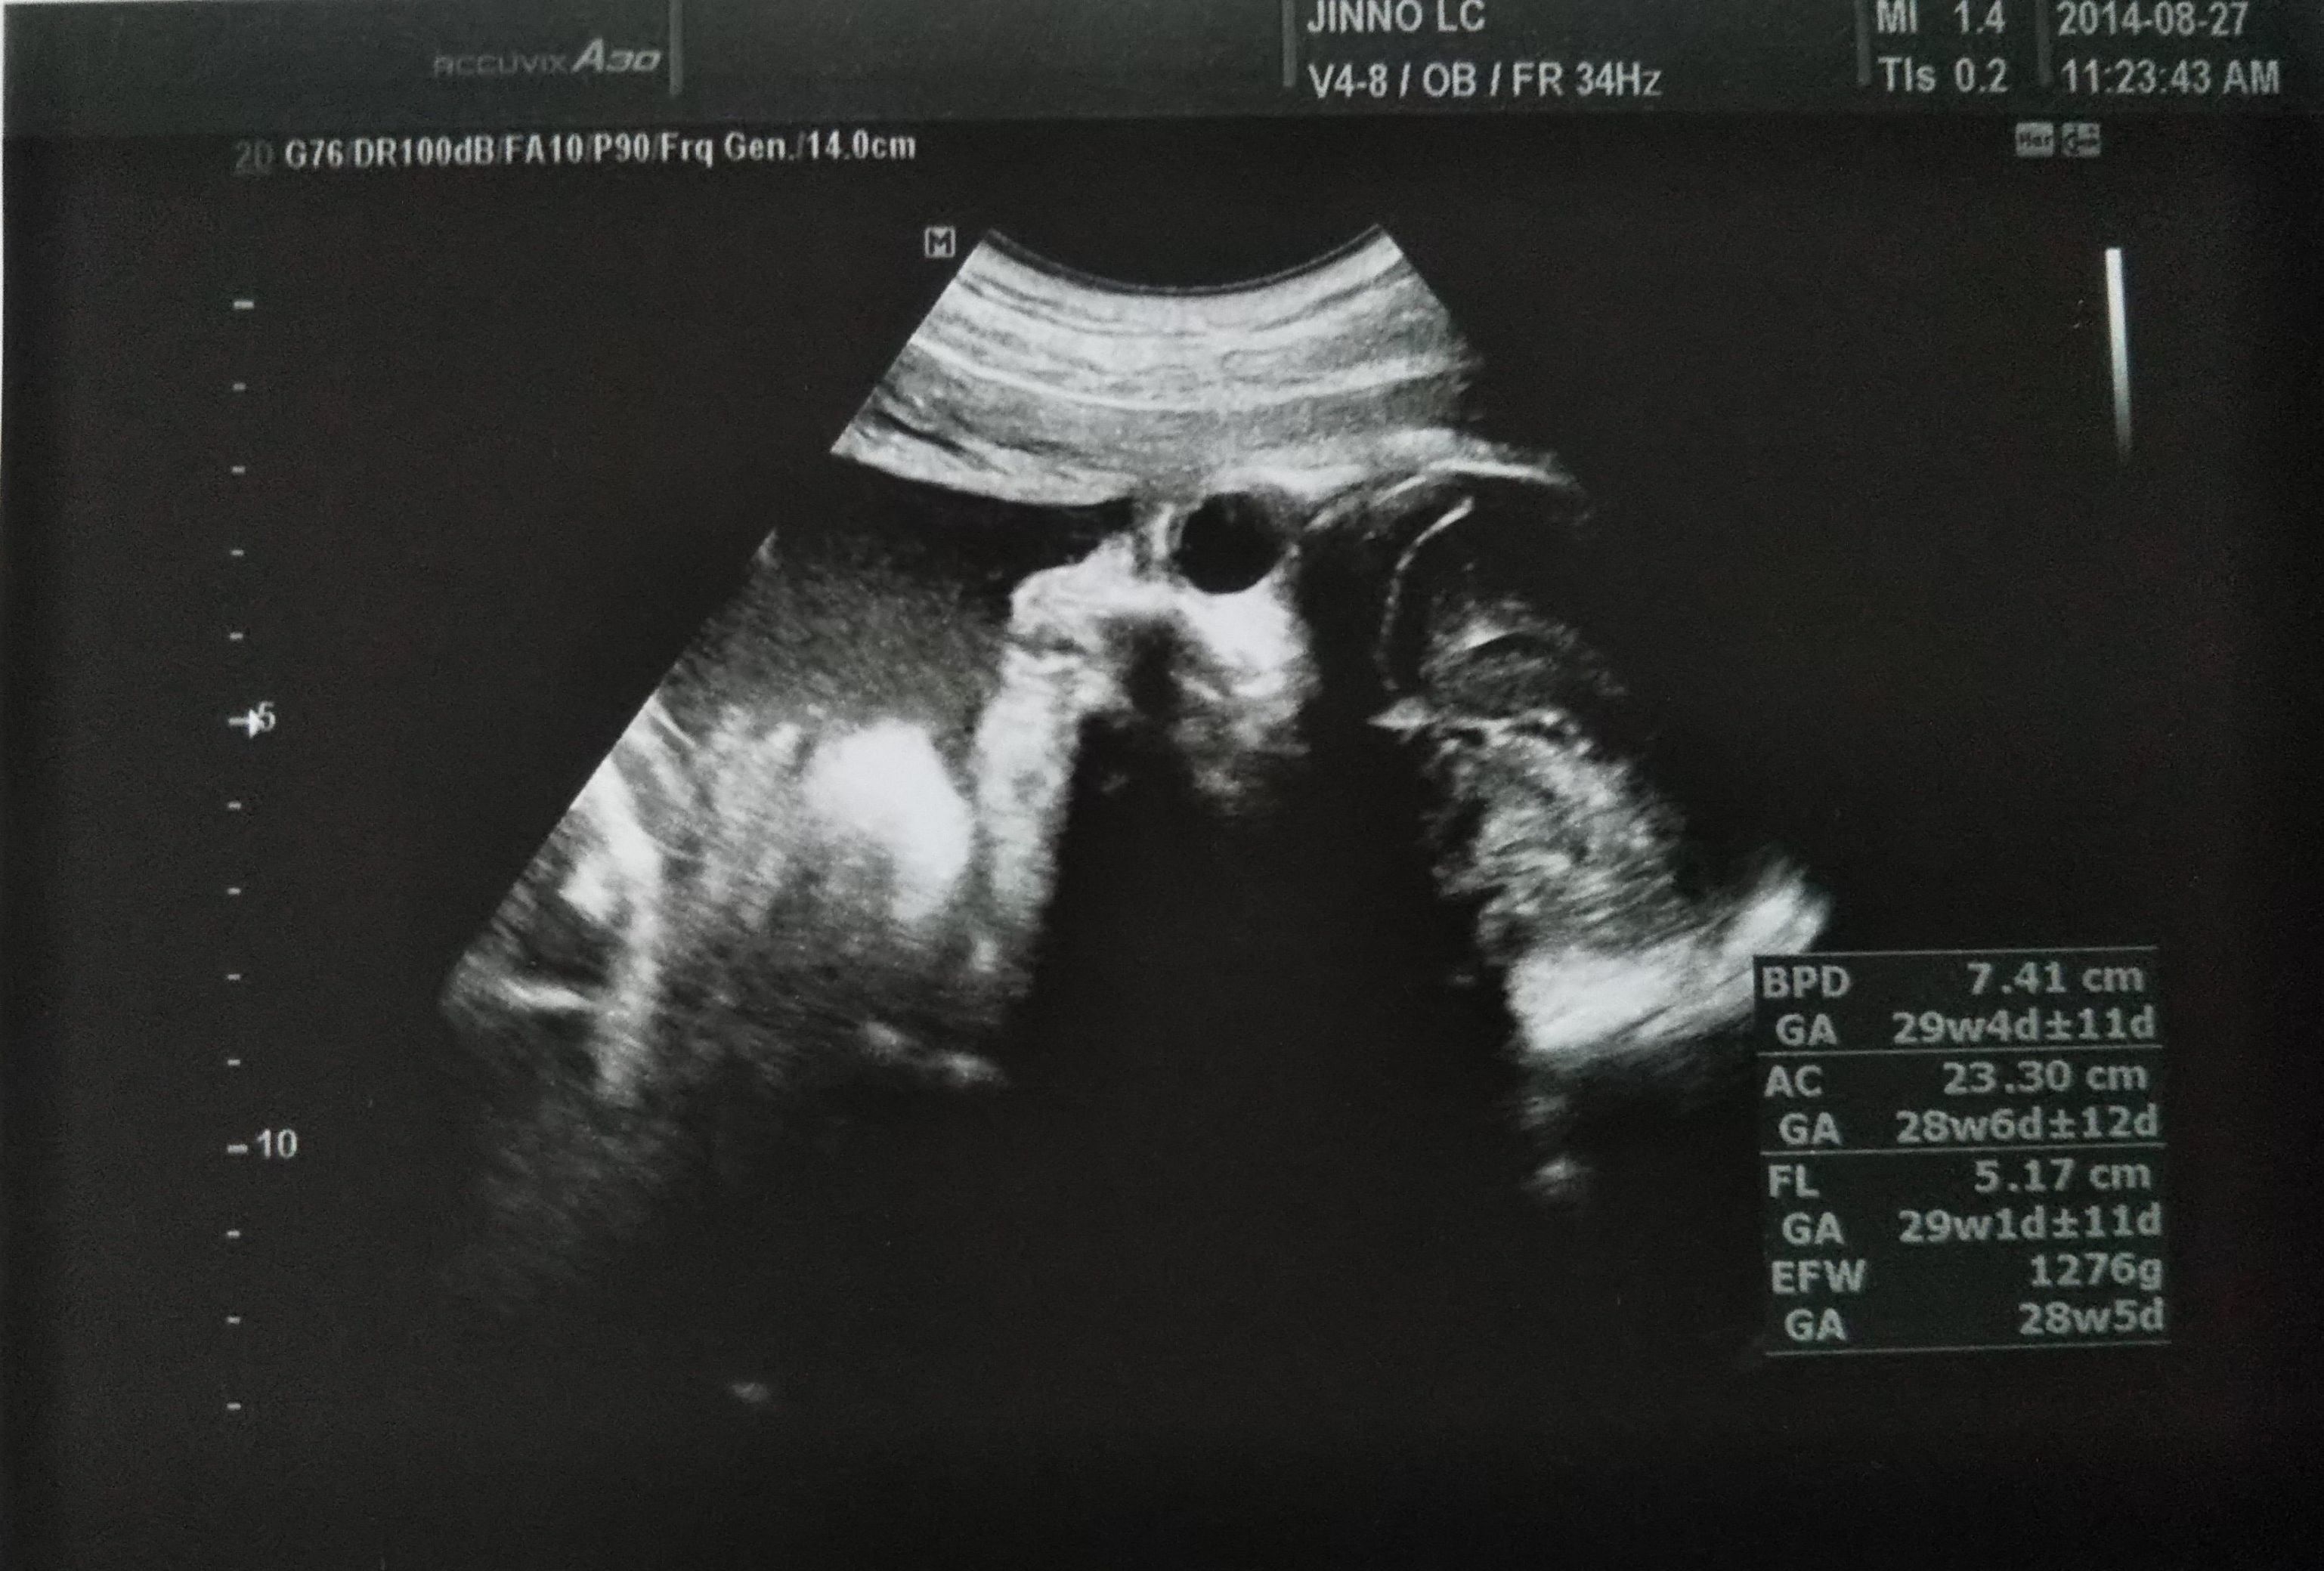

妊娠37週目のエコー写真 子宮口は1cm未満。運動が足りないと言われてしまいます

37週目。子宮口の開きが前回と同じ1㎝未満。先生から、「もっと運動するように」と言われました。出産が急に怖くなって、「怖い、怖い」とばかり思っていたけれど、友人がプレゼントしてくれた絵本を読んで、出産に対して考え方が少し変わって楽になりました。もうエコーを取っても、赤ちゃんの様子がはっきり見られないからということで、これが最後のエコー写真となりました。